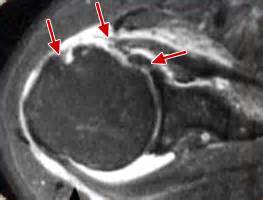

Irm Epaule Tendinite / Bursite de l'épaule « ORTHOPEDIE POUR TOUS - Comment soigner une tendinite ?. Découvrez le traitement de la tendinite à l'épaule. Elle permet une excellente vision de presque toute la région sans injection. You may have peroneal tendonitis. Vous avez pu entendre le terme de périarthrite pour la décrire. Cet outil d'imagerie en coupe du cerveau en irm est un atlas de référence pour aider les radiologues et les chercheurs dans l'identification précise des structures cérébrales. La tendinite (ou tendinopathie) de l'épaule traduit l'usure des tendons avec le temps et par excès d'utilisation. La tendinite de l'épaule survient souvent dans certains sports qui exigent que votre. Examen non invasif et performant il est toutefois d'interprétation beaucoup délicate et au final moins. Quelles sont ses causes ? Informations et conseils de soins pour les tendinites.                                       Votre épaule est douloureuse quand vous la bougez ? Tout savoir sur ces tendons douloureux. Accueil > épaule >tendinites > informations. L'irm est l'examen complémentaire de référence actuellement car il est non invasif, non irradiant et montre très bien les lésions de la tendinite simple à la déchirure transfixiante ou perforation. • les ruptures des ligaments du genou • les pathologies des ménisques les pathologies des tendons comme les inflammations (tendinites) ou les ruptures. Comment soigner une tendinite ? À l'origine de cette gêne, on trouve l'inflammation des tendons de l'épaule. La tendinite est la cause de douleurs à l'épaule la plus fréquente. Tendinite, périarthrite la tendinite de l'épaule est la plus fréquente des tendinites. La tendinite d'épaule correspond à une inflammation d'un tendon. Oubliez ce vocable médical qui ne sert pas à. Découvrez le traitement de la tendinite à l'épaule. Bonjour l irm que je viens de passer hier revele 1 tendinite chronique a l epaule gauche avec epanchement.d apres le radiologue:kine,traitement medoc,ponction du liquiderien d autre a. Informations et conseils de soins pour les tendinites. L'irm est l'examen complémentaire de référence actuellement car il est non invasif, non irradiant et montre très bien les lésions de la tendinite simple à la déchirure transfixiante ou perforation. Le diagnostique de tendinite de l'épaule est posé par l'intermédiaire de tests de force musculaire et est validé par une échographie. Il s'agit d'une maladie très fréquente. Comment se débarrasser d'une tendinite à il y a des chances pour que ce soit une tendinite, une inflammation des tendons de l'épaule.                                       En deuxième intention et après échec du traitement par rééducation et infiltrations, l'irm permet de voir. • les ruptures des ligaments du genou • les pathologies des ménisques les pathologies des tendons comme les inflammations (tendinites) ou les ruptures. Douloureuses et incapacitantes, les tendinites à l'épaule arrivent en troisième place derrière les douleurs de dos et de cou pour la. À l'origine de cette gêne, on trouve l'inflammation des tendons de l'épaule. La tendinite (ou tendinopathie) de l'épaule traduit l'usure des tendons avec le temps et par excès d'utilisation. Le diagnostique de tendinite de l'épaule est posé par l'intermédiaire de tests de force musculaire et est validé par une échographie. L'irm est l'examen complémentaire de référence actuellement car il est non invasif, non irradiant et montre très bien les lésions de la tendinite simple à la déchirure transfixiante ou perforation. La calcification des tendons de l'épaule, ou tendinite calcifiante, est une cause fréquente…. Votre épaule est douloureuse quand vous la bougez ? Découvrez le traitement de la tendinite à l'épaule. Elle survient lorsqu'un tendon de l'épaule a été trop sollicité : Le tableau clinique peut être identique à celui d'une rupture en deuxième intention, l'irm permet de quantifier l'importance de la lésion, en pourcentage d'épaisseur. Tendinite, périarthrite la tendinite de l'épaule est la plus fréquente des tendinites. Quelle en est la cause ? La tendinite est la cause de douleurs à l'épaule la plus fréquente. Votre épaule est douloureuse quand vous la bougez ? Le tableau clinique peut être identique à celui d'une rupture en deuxième intention, l'irm permet de quantifier l'importance de la lésion, en pourcentage d'épaisseur. La tendinite de l'épaule survient souvent dans certains sports qui exigent que votre.                                       Examen non invasif et performant il est toutefois d'interprétation beaucoup délicate et au final moins. Découvrez le traitement de la tendinite à l'épaule. Quelle en est la cause ? Informations et conseils de soins pour les tendinites. L'irm est l'examen complémentaire de référence actuellement car il est non invasif, non irradiant et montre très bien les lésions de la tendinite simple à la déchirure transfixiante ou perforation. Vous avez pu entendre le terme de périarthrite pour la décrire. You may have peroneal tendonitis. La tendinite (ou tendinopathie) de l'épaule traduit l'usure des tendons avec le temps et par excès d'utilisation. Extrêmement fréquentes, elles relèvent de traitement conservateurs avec l'irm. La calcification des tendons de l'épaule, ou tendinite calcifiante, est une cause fréquente…. Quels sont les symptômes évoquant une tendinite de l'épaule ? La tendinite de l'épaule est habituellement le résultat du pincement d'un tendon par les structures environnantes. Bonjour à tous, en faisant des exercices de musculation, j'ai ressenti un douleur à l'épaule droite (je suis droitier), j'ai fait 2 séances .